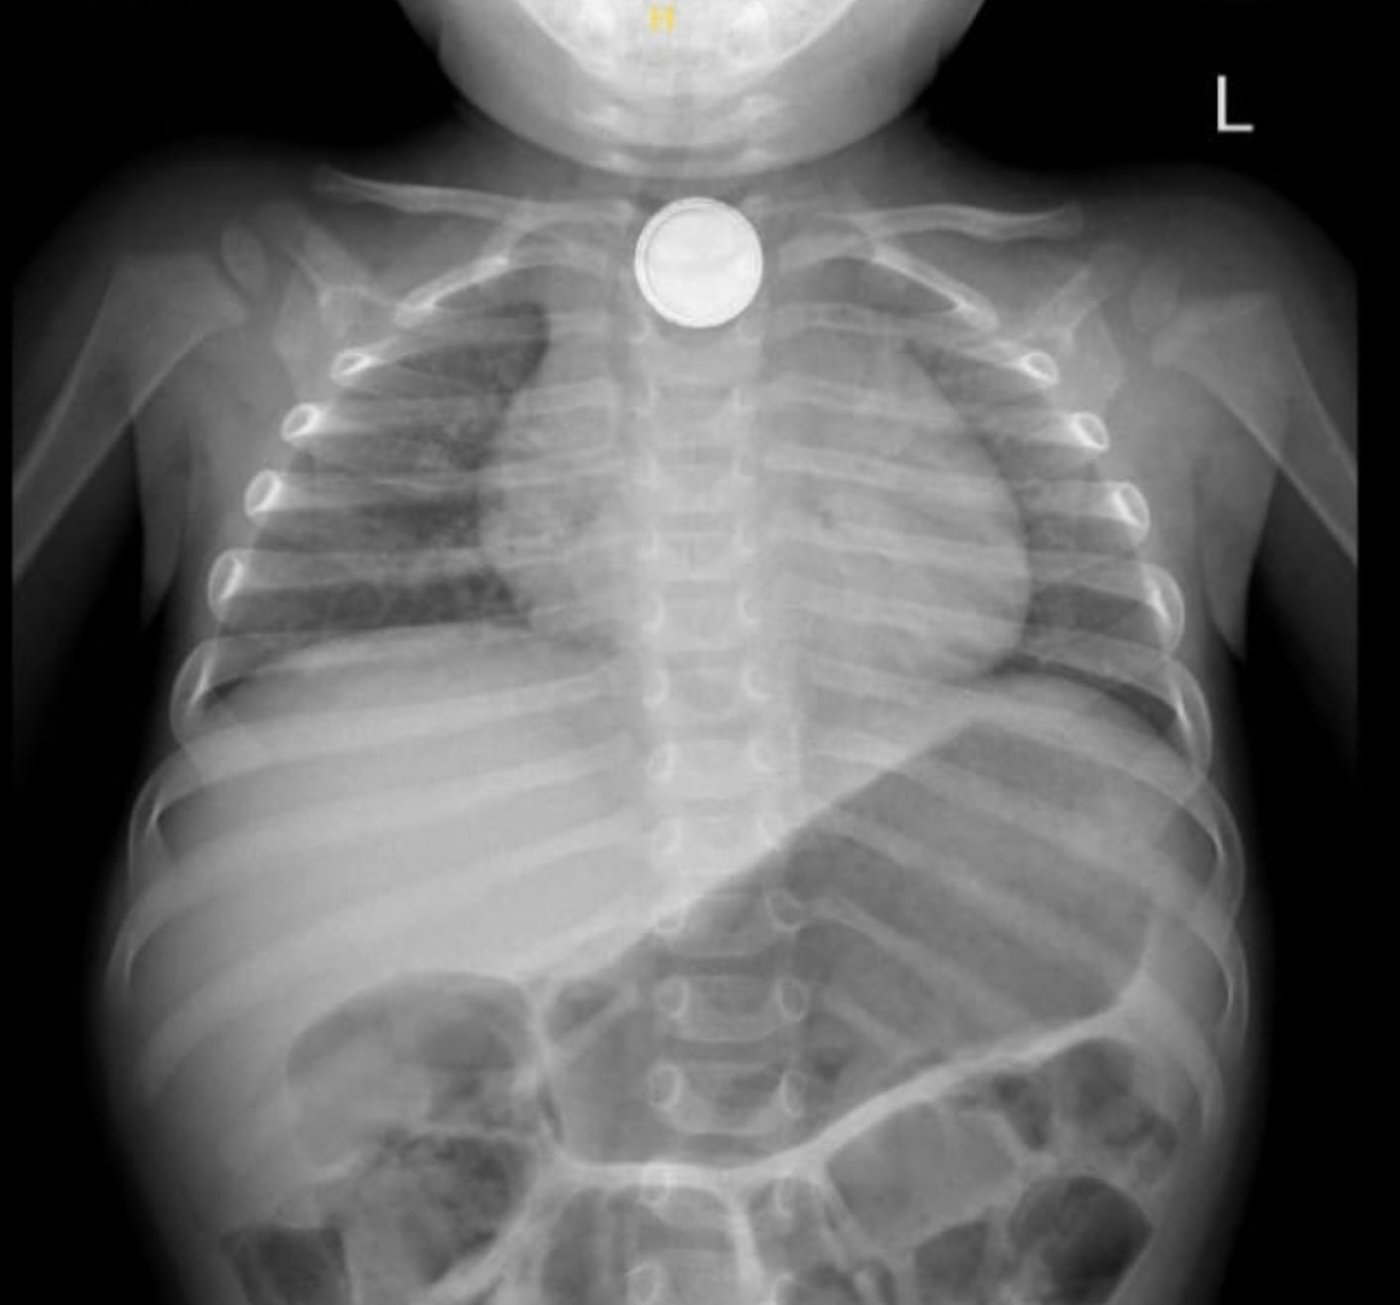

ד"ר דניאל כהנא, מתמחה ברפואת ילדים, קיבלה את הפעוט במלר"ד הילדים וזיהתה במהירות את חומרת המצב. בצילום רנטגן אובחנה הסוללה בוושט העליון, ממצא שהצריך טיפול דחוף. בתוך זמן קצר הוזעק צוות גסטרו ילדים, ניתן טיפול ראשוני בדבש – טיפול ייעודי למקרים של בליעת סוללה למניעת נזק לרקמה – והפעוט הועבר באופן מיידי לחדר ניתוח.

כחצי שעה בלבד מרגע כניסתו למיון, כבר החלה הפעולה להוצאת הסוללה בגסטרוסקופיה דחופה שבוצעה על ידי ד"ר איתן דמארי, מומחה בגסטרו ילדים וסגן מנהל מחלקת הילדים, יחד עם האחות יוליה מלכי. במהלך הפעולה התגלה כי בשל השהות הממושכת נגרמה כוויה נרחבת בוושט.